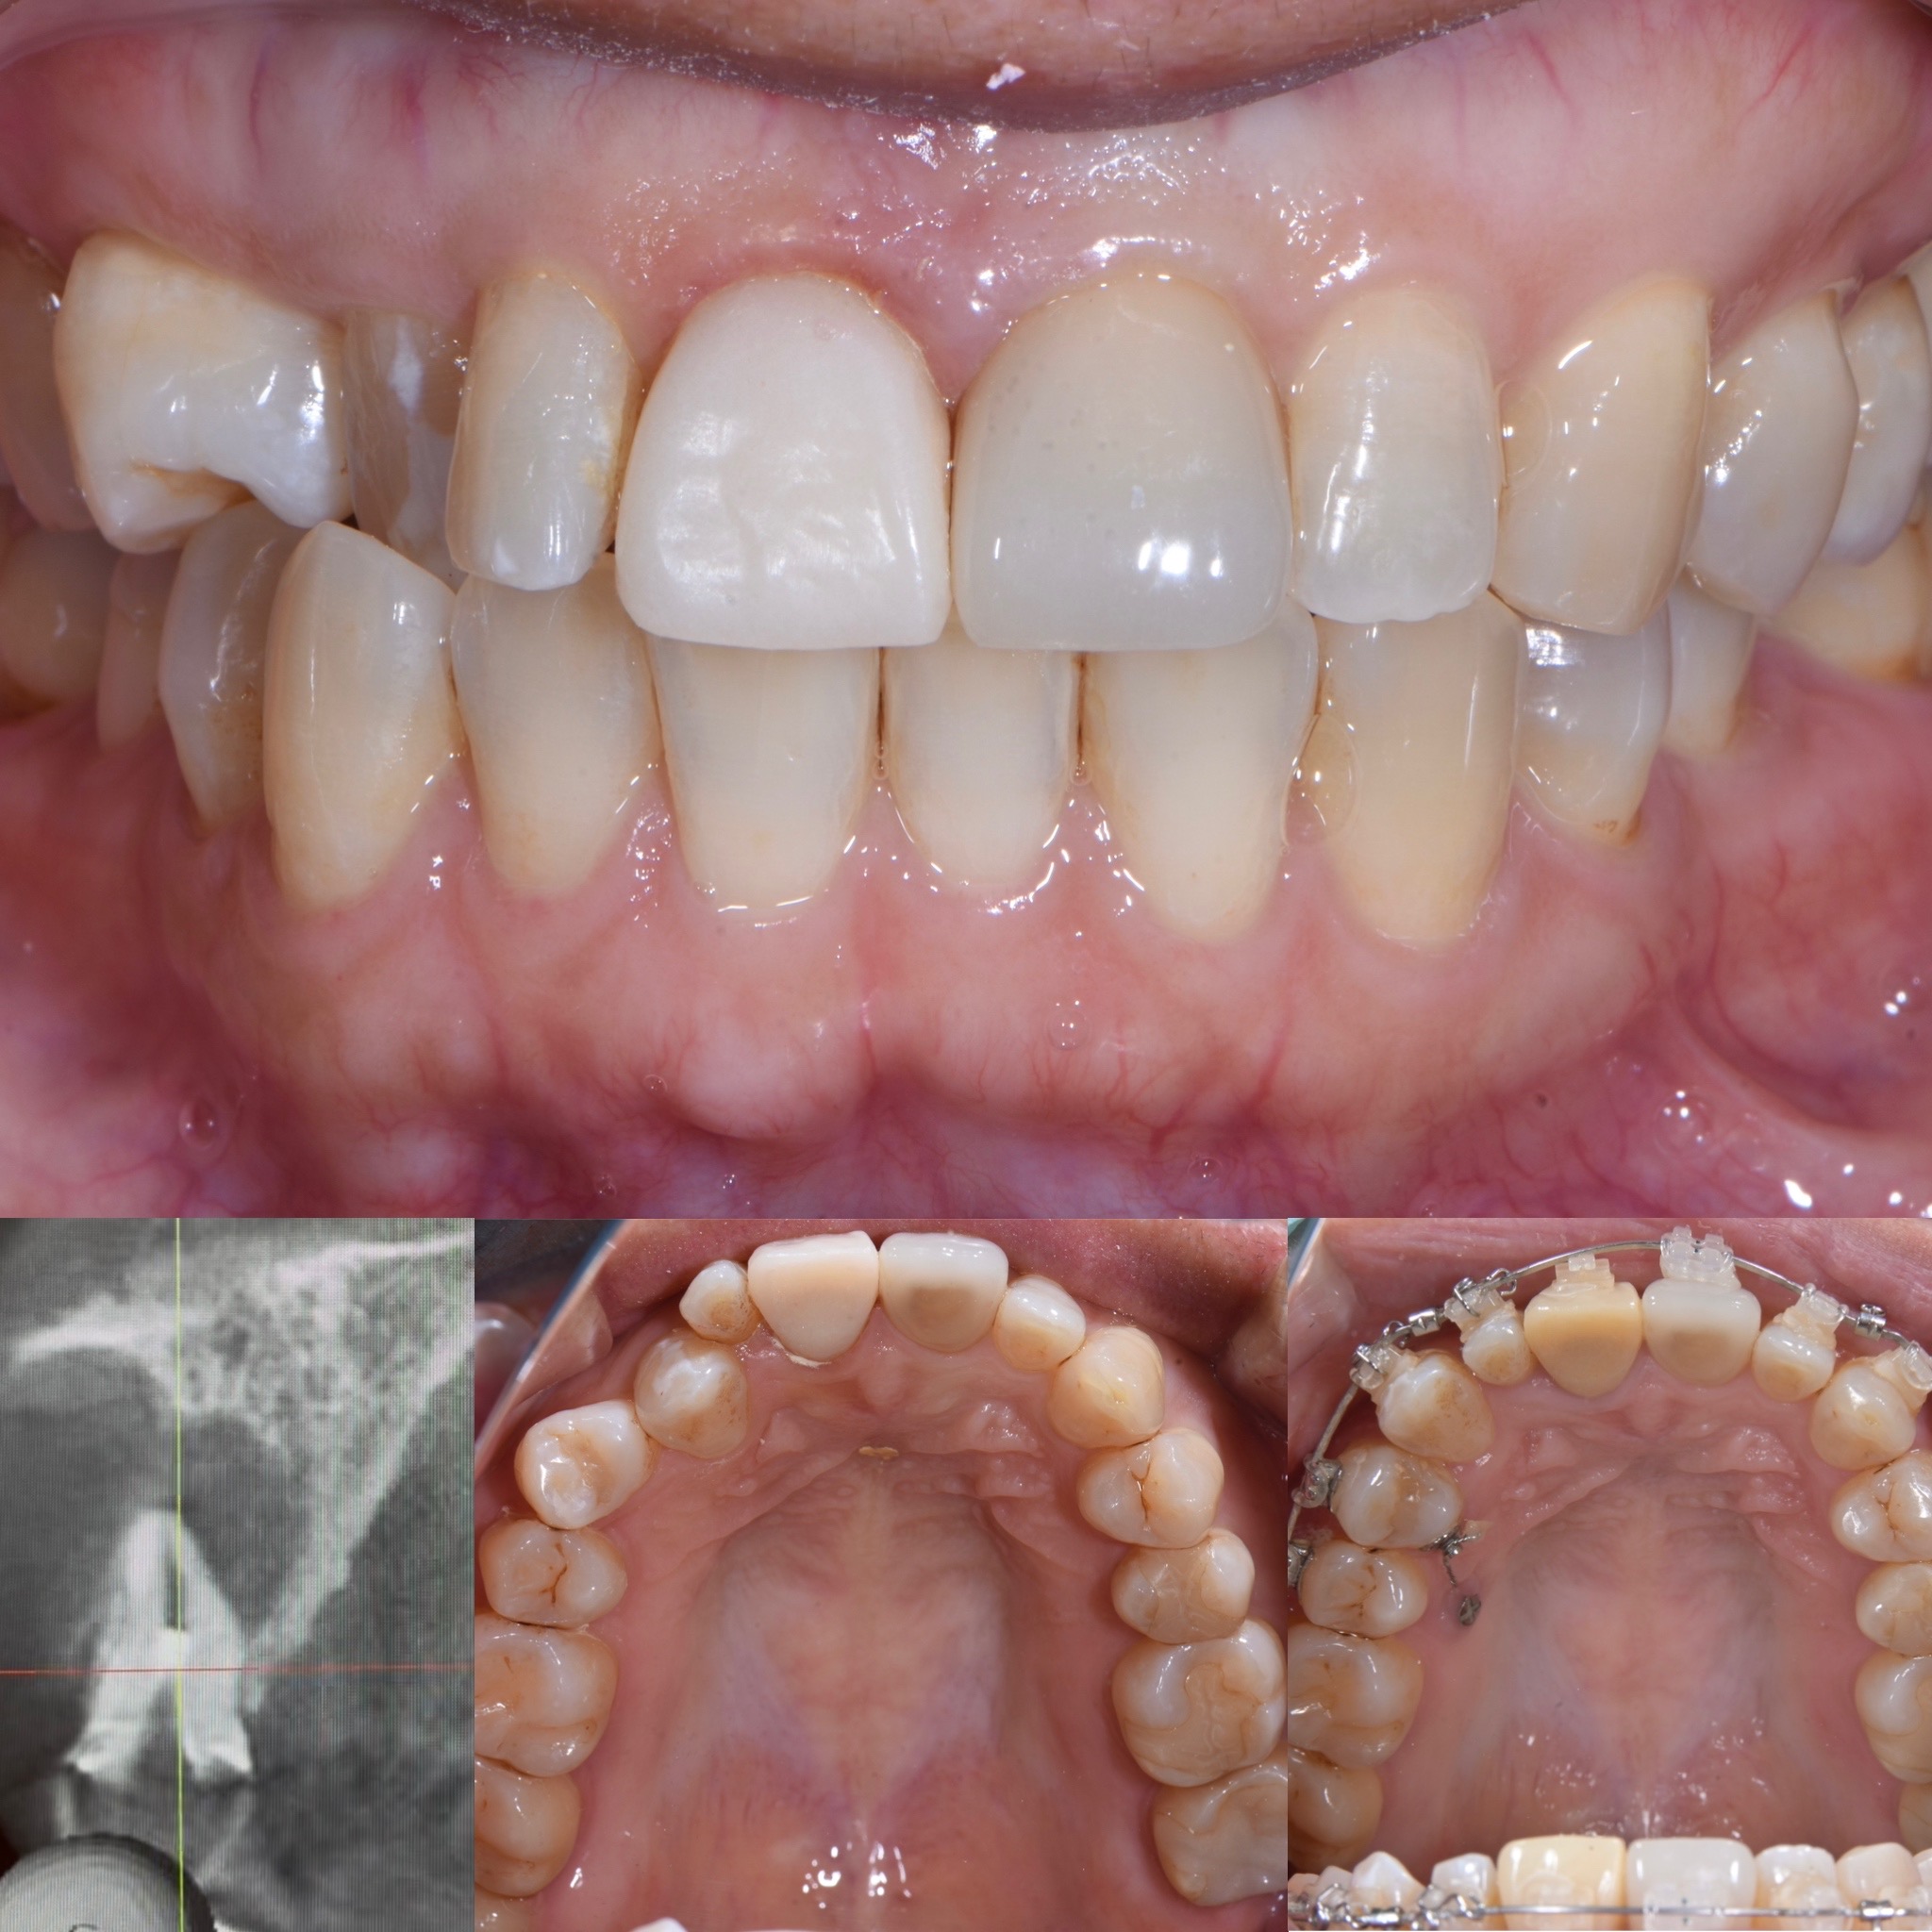

歯周病が進行した前歯に対する包括的治療〜エムドゲインを使用した歯周組織再生療法

- 主訴

- 最近 前歯に隙間で出来て、歯が動く(動揺)することを主訴に来院されました。

- 治療内容

- 歯周病から歯を支える骨(歯槽骨)の喪失を起こし歯牙移動と動揺を呈していた右側上顎中切歯に人工骨とエムドゲインを使用した歯周組織再生療法を行いました。

歯牙の位置異常に対しては部分矯正治療を行っています。

- 治療期間

- 12ヶ月

- 治療費用

- 歯周再生療法 110,000円 部分矯正治療 440,000円

- 治療のリスク

- 歯周病に対するブラッシング指導など基本治療を行い、再生療法を行うことで吸収していた歯槽骨の再生をレントゲンで確認することができました。

今後、定期的なメインテナンスが必要となります。怠ると再発リスクが高まります。

条件によっては歯槽骨の再生が予定より少なくなることがあります。

BEFORE

AFTER